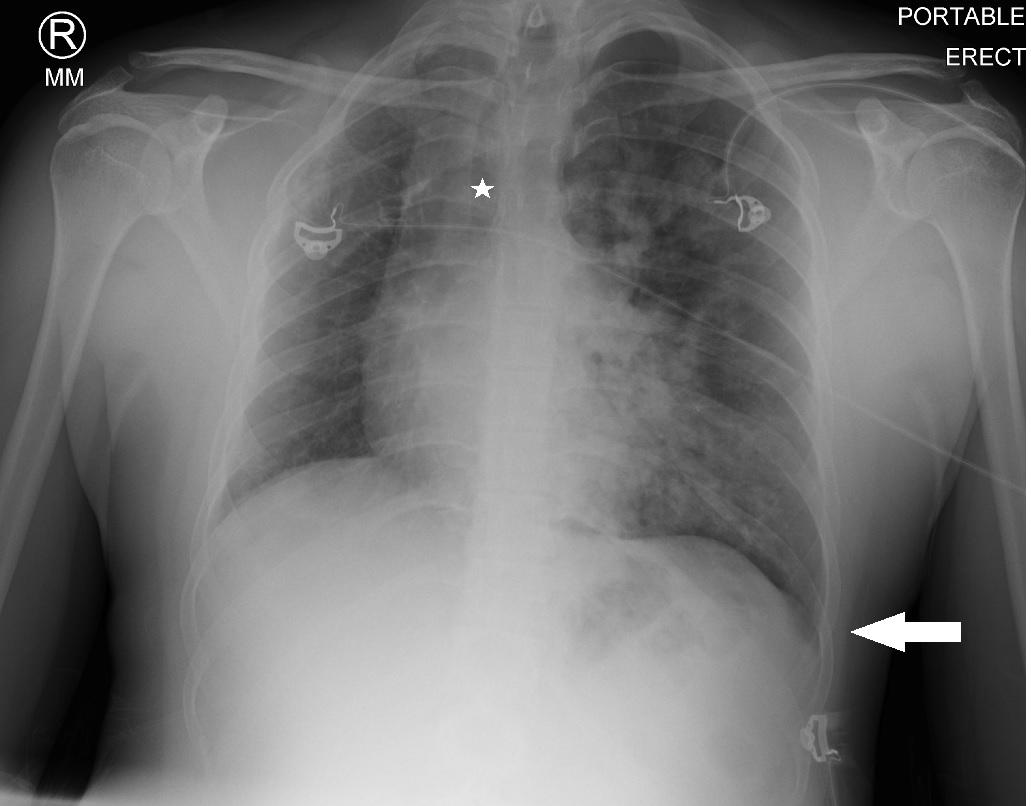

Given these findings, the patient was suspected to be in acute respiratory failure due to severe bronchiolitis. As the patient presented early at the onset of the coronavirus disease 2019 (COVID-19) pandemic, COVID-19 remained high on the differential, given little was known regarding its effects on infants. Oxygen was administered via non-rebreather (NRB) mask with broad spectrum antibiotics and intravenous fluids (IVF) due to concern for sepsis. His labs were notable for white blood cell count of 10.6 x 103 per millimeter (mm3) (reference range: 5x103 - 10x103 mm3) with a lymphocytic predominance; hemoglobin 20.4 grams (g) per deciliter (dL) (14-17 g/dL); creatinine of 0.4 milligrams (mg)/dL (0-0.5 mg/ dL); and a lactate of 12.5 millimoles per liter (mmol/L) (0-4 mmol/L). A COVID-19 polymerase chain reaction test was negative. Chest radiograph was interpreted by the emergency physician as technically limited due to rotation with diffuse prominent interstitial markings concerning for viral pneumonia (Image 1).

Addepalli et al. Point-of-care Ultrasound Diagnosis of Tetralogy of Fallot Causing Cyanosis: A Case Report Image 1. Portable anteroposterior chest radiograph showing no focal infiltrate and limited due to patient rotation.